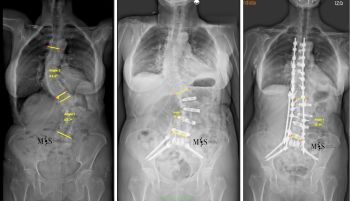

L'equip quirúrgic del Centro Médico Teknon, liderat pel Dr. Christian Morgenstern, director del Morgenstern Institute of Spine al Centro Médico Teknon, ha intervingut amb èxit una pacient de 80 anys afectada per una escoliosi degenerativa dorsolumbar severa. El cas, que presentava una curvatura de 57º a la zona lumbar i 42º a la dorsal, ha estat resolt mitjançant la tècnica ACR (correcció de columna anterior) en dos temps.

La intervenció es va dividir en dos temps quirúrgics per maximitzar la seguretat. En una primera fase, es van realitzar abordatges mínimament invasius per via anterior i lateral per rectificar parcialment la columna, per la qual cosa es va aconseguir reduir la corba lumbar de 56 º a 39 º de forma immediata. Aquesta correcció prèvia va permetre que la segona fase, realitzada per via posterior, fos molt menys agressiva i es pogués executar de forma percutània.

Per garantir la seguretat en una anatomia tan complexa, on les vèrtebres presentaven rotacions tridimensionals i pedicles molt fins, es va fer servir tecnologia de neuronavegació i TAC intraoperatori (O-Arm). Aquestes eines permeten una col·locació mil·limètrica dels implants i minimitzen el risc de lesions nervioses o vasculars. En casos com aquest, aquest tipus de tecnologies tenen un paper clau. Segons apunta el Dr. Morgenstern "en les rotoescoliosis complexes com aquesta l'anatomia pot ser molt variable i complexa, ja que les vèrtebres estan molt rotades en un espai tridimensional. A més, els pedicles poden ser displàsics, molt fins o molt fràgils. La neuronavgeació amb el TAC intraoperatori permet una col·locació molt més segura dels cargols transpediculars en anatomies tan complexes en oferir imatges en les 3 dimensions anatòmiques".